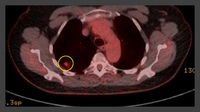

PET-CT com 18-fluordesoxiglucose (18-FDG) mostrando lesão periférica de alta captação no pulmão esquerdo. A ressecção cirúrgica confirmou câncer pulmonar de células escamosas moderadamente diferenciado

PET-CT com 18-fluordesoxiglucose (18-FDG) mostrando baixa captação em lesão semissólida posterior no lobo superior direito. A ressecção cirúrgica confirmou adenocarcinoma com padrão primariamente lepídico